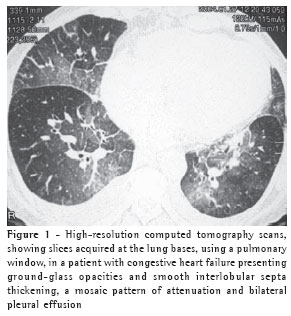

Peribronchovascular interstitial thickening was observed in twelve cases (80%), being bilateral in ten (Figure 4) and unilateral in two (the cases of fibrosing mediastinitis).

Peribronchovascular interstitial thickening was seen in twelve patients (80%). In ten patients, the thickening was bilateral and smooth. In the two cases of fibrosing mediastinitis, the peribronchovascular interstitial thickening was unilateral. Such thickening is identified by determining the thickness of the bronchial walls. The presence of peribronchovascular interstitial thickening reflects, for hydrostatic edema patients, drainage of the fluid via central interstitial pathways.(3) Em outro estudo,(9) o espessamento foi achado na tomografia computadorizada de alta resolução em quatro de sete pacientes.

In another study,(9) such thickening was detected in the high-resolution computed tomography scans in four of seven patients.